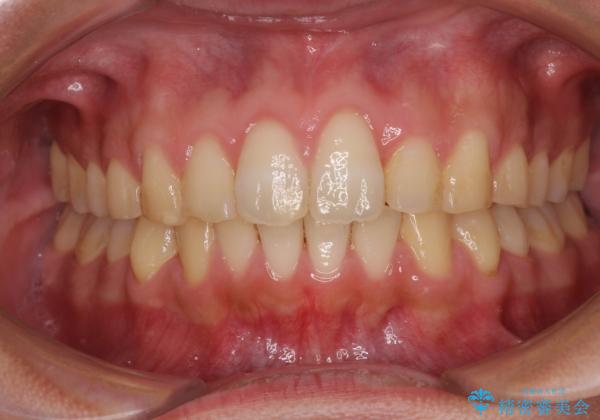

捻れて飛び出した前歯 インビザラインで整った前歯に

歯と歯の間を削ることでうまくスペースコントロールでき、また、毎日22時間以上しっかりとマウスピースを装着していただいたので、スムーズに治療が進みました。

治療途中で転勤となり、遠方からの通院となったため、来院間隔空いてしまいましたが、2年間で終えることができました。